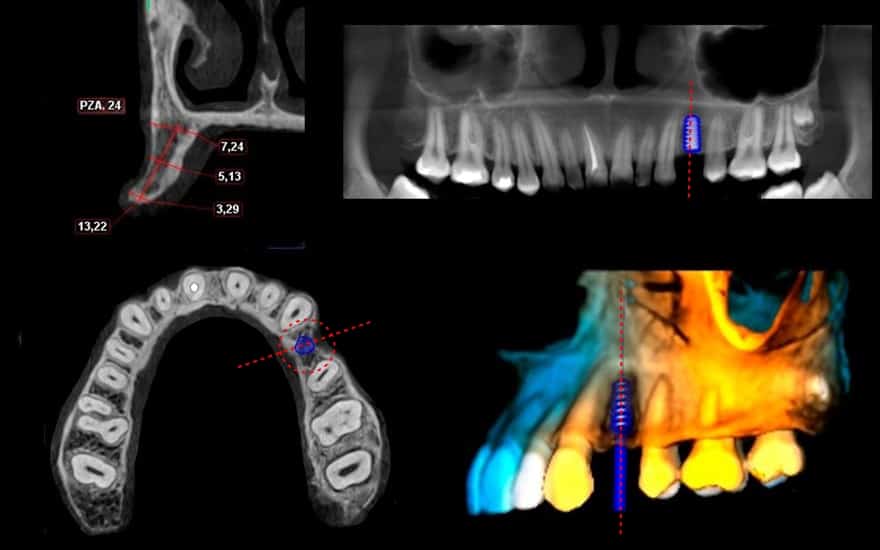

1. Tomografía CONE BEAM

Es una tomografía especial para odontología y se caracteriza por ser muy precisa y con detalles anatómicos milimétricos.

Permite evaluar la cantidad (volumen) y calidad de hueso necesario para poder colocar el implante. La principal razón por la que NO es posible colocar el implante en boca, es por la falta de hueso de soporte.